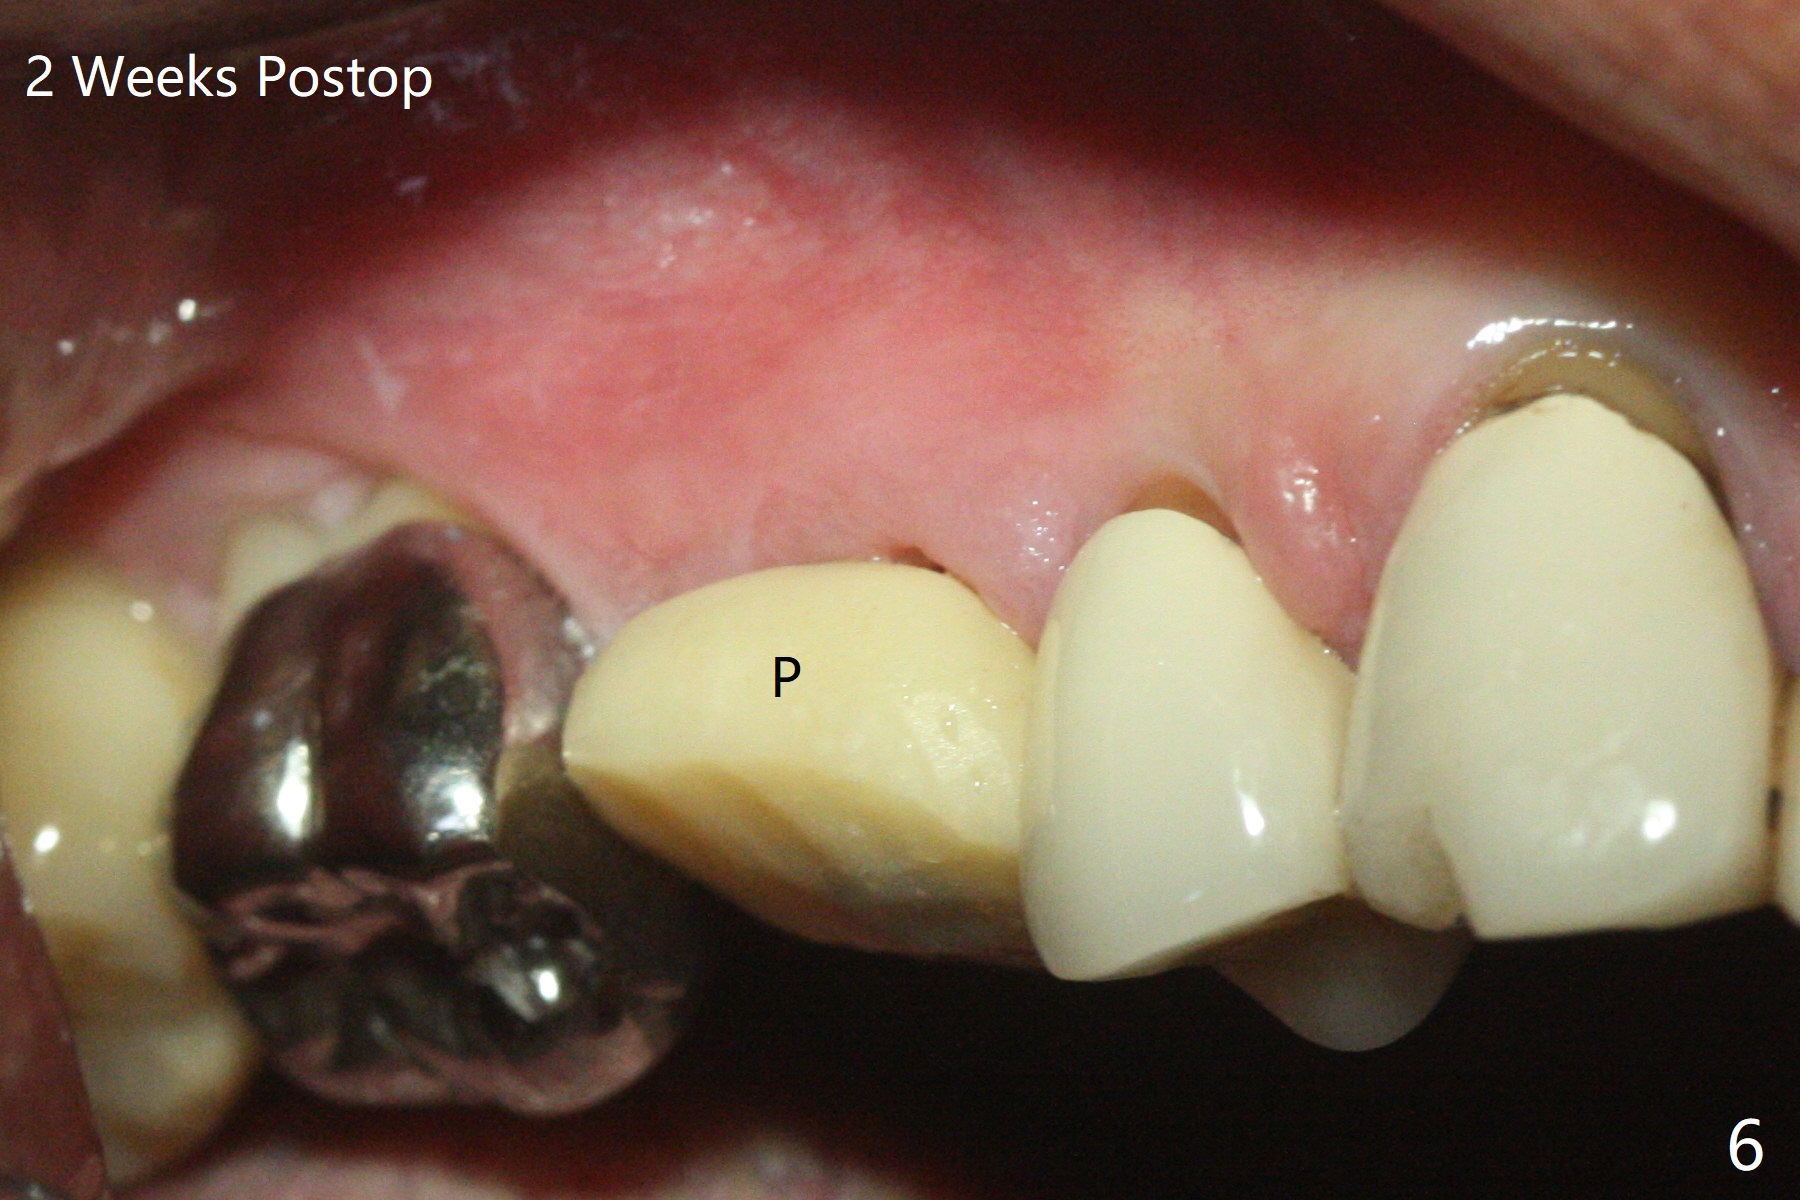

After flattening the root stump with surgical burs and bone trimmer at #4 (Fig.1), it is difficult to use point drill and 2.2x7.3 mm drill because of incomplete engagement of drill cylinder with guide sleeve (Fig.2). The initial osteotomy seems to be buccal. With removal of the remaining root, it is much easier to finish osteotomy (better engagement of drill cylinder with the sleeve) and sinus lift with dummy implants (Fig.3,4 (*: bone graft)). Finally a 4.5x10 mm implant is placed (basically in the middle of the socket with even buccal and palatal gaps) with primary stability and a cemented abutment is hand tightened (after 5.5 mm profile drill) for an immediate provisional (Fig.5). The gingiva is healthy around the provisional with almost perfect seal 2 weeks postop (Fig.6 P). There is no obvious bone loss 7 months postop (Fig.7). There is apparent mature bone in the sinus 9 months postop (Fig.8 *).